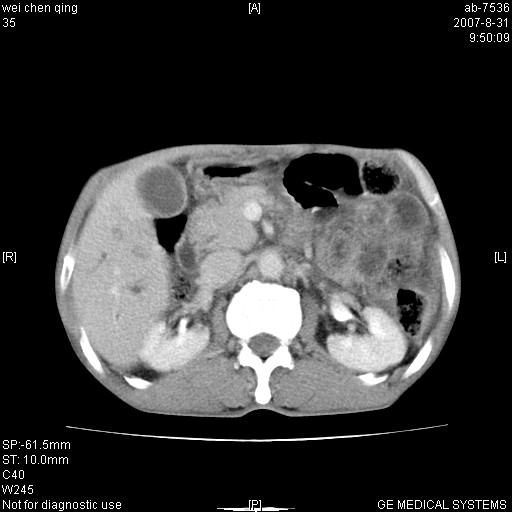

以下是引用zjzjr在2007-8-31 14:38:00的发言:[br]胰头癌伴肝内胆管扩张可能性大。

以下是引用zyyzzy在2007-8-31 14:34:00的发言:[br]该病人肝内胆管扩张,胆囊及胆总管未见明显扩张。在倒数第9层图像上可看到左右肝管结合部(肝总管)有软组织影,此处应薄层扫描。考虑肝总管占位(ca)、腹水。[br]